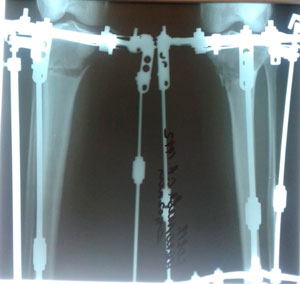

Исходник - 27 лет. Якутия.

Дата операции - 12.07.2019г.